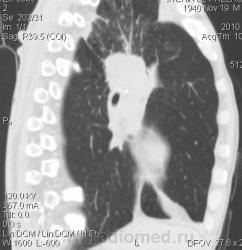

Мужчина 69 лет, с последствием ОНМК находился в доме-интернате для инвалидов. В анамнезе пневмония справа и исходом в пневмосклероз. ФЛГ не проходил 1.5 года. Анализы: СОЭ 20 мм/ч, остальное - без особенностей. Поступил в неврологическое отделение с диагнозом: повторное ОНМК. Невролог заподозрил метастазы головного мозга, направил на рентгенографию легких. После выявленых изменений в правом легком, пациент направлен на КТ головного мозга и грудной полости. От контрастирования и бронхоскопии категорически отказался.

По поводу подозрения на туберкулез пациента в прошлом нодократно проверяли, исключили. ФЛГ архива у меня нет. Все только со слов пациента. Кальцинаты в корне массивные. Трудно сказать, откуда опухоль (если это не конгломерат лимфоузлов!) плотностью 35 ед.Н - то ли из вехнедолевого бронха, который имеет культю 0.4 см и заканчивается выпуклым контуром, но при этом сохраняется воздушность почти всей доли; то ли периферический с центром в прикорневой зоне и вторичным прорастанием ВДБ. К сожалению забыла про снимок легких, на днях выставлю. Я первоначально считала периферический (верхушка, на фоне пневмосклероза) с мтс средостения. По плотности на верхушке узелок 5 ед.Н, только поэтому засомневалась, где же первичный. Лимфоузлы средостения множественные, до 2 см. Кроме того, на верхней стенке правого главного бронха есть мелкое образование такой же 35 е.Н плотности, то ли аденома, то ли прорастает... Без бронхоскопии - только гадать

это периферический рак S2 в/доли правого легкого с мтс во внутригрудные л/узлы.

А тут нечего гадать - данную демонстрацию можно поместить в учебник: узловое образование, с бугристыми, лучистыми контурами, связаное с плеврой, "дорожкой" к корню, перифокальной инфильтрацией. Корень расширен полицикличен за счет конгломерата увеличеных бронхопульмональных, трахеобронхиальных и бифуркационных л/узлов, значительно сдавливающих в/долевой бронх, с нарушением вентиляции в/доли.

Центральный рак ВДБ справа с мтс в л/узлы паратрахеальные нижние, верхние справа, БФ. МТС в головной мозг. А про печень мало сканов

Мне кажется в 6 сегменте печени мтс + еще мтс поражение левого надпочечника вероятнее всего. Мтс в нижние паратрахеальные (с обеих сторон)+бифуркационные л/у. Поражения верхних паратрахеальных не вижу (на коронарах), аксиалы - не показыны сканы выше верхнего края дуги аорты, так что я бы не говорил про поражение верхних медиастинальных лимфоузлов (хотя тут это уже не принципиально) + мтс в головной мозг. А так - центральный рак правого легкого.